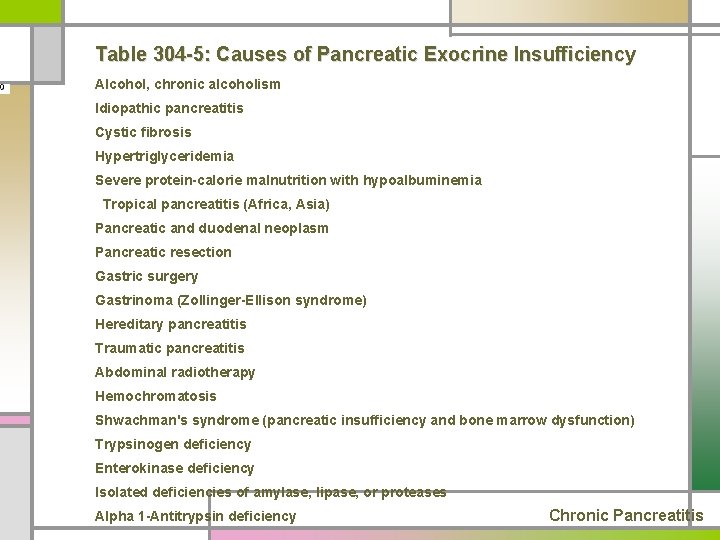

Table 304 -5: Causes of Pancreatic Exocrine Insufficiency Alcohol, chronic alcoholism Idiopathic pancreatitis Cystic fibrosis Hypertriglyceridemia Severe protein-calorie malnutrition with hypoalbuminemia Tropical pancreatitis (Africa, Asia) Pancreatic and duodenal neoplasm Pancreatic resection Gastric surgery Gastrinoma (Zollinger-Ellison syndrome) Hereditary pancreatitis Traumatic pancreatitis Abdominal radiotherapy Hemochromatosis Shwachman's syndrome (pancreatic insufficiency and bone marrow dysfunction) Trypsinogen deficiency Enterokinase deficiency Isolated deficiencies of amylase, lipase, or proteases Alpha 1 -Antitrypsin deficiency Chronic Pancreatitis